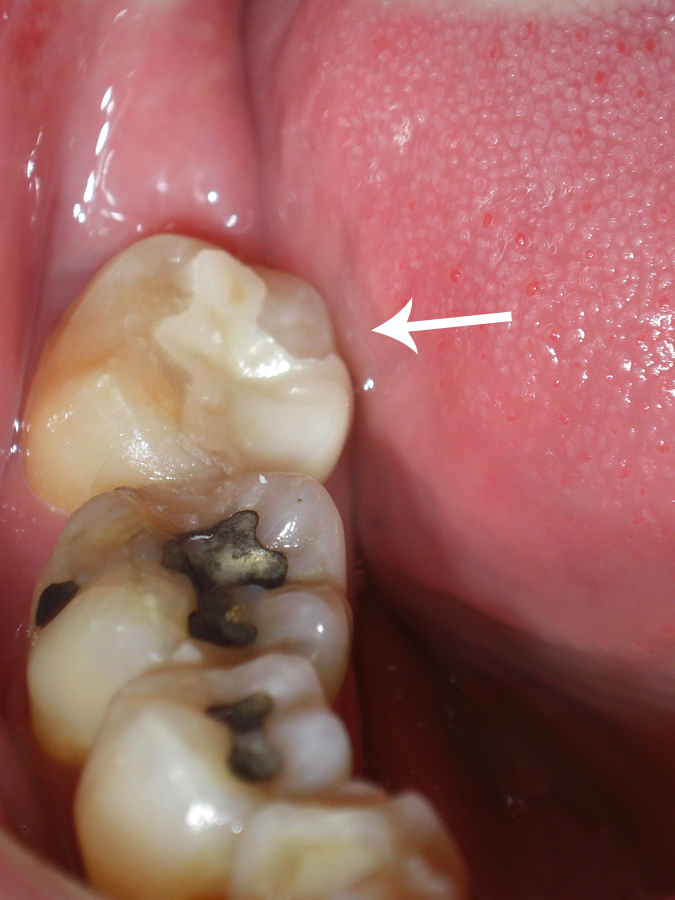

50代男性(右下7番)広陵町在住

〔術前〕

外国出張がある時期に”仮歯”が取れ一度治療して頂きました。

その後、最終治療まで大丈夫でしたがいつもまた取れるのではないかとビクビクしていました。